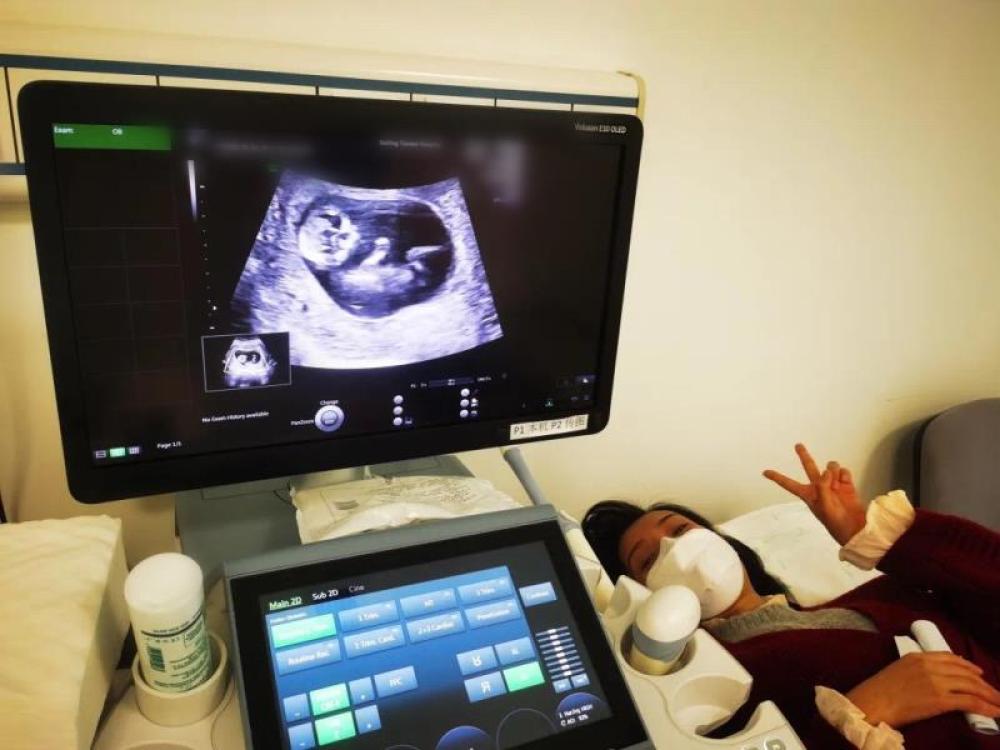

今天一早,妻子去醫(yī)院進(jìn)行B超檢查,同事用手機(jī)拍攝下了B超顯示屏上的畫面,記錄下了這個(gè)87天的小家伙第一次“亮相”。

圖為北京天壇醫(yī)院袁磊愛(ài)人做B超檢查。

“袁磊,看看你們家寶寶,可愛(ài)嗎?”收到同事發(fā)來(lái)的視頻,第一眼就看哭了,身邊的同事看完視頻也哭了。

視頻里,這個(gè)小家伙好像聽到了外面的召喚,在媽媽的肚子里伸手、踢腿、翻身,用各種動(dòng)作進(jìn)行回應(yīng)……看到他那小胳膊小腿,一種從未有過(guò)的幸福感不停地向上涌,眼淚怎么也控制不住。

其實(shí)在武漢這么多天,他一直就是我的牽掛,今天終于看到他了,那種感受真是又緊張又激動(dòng),雖然還看不清他的樣子,但是已經(jīng)感受到他的活力。